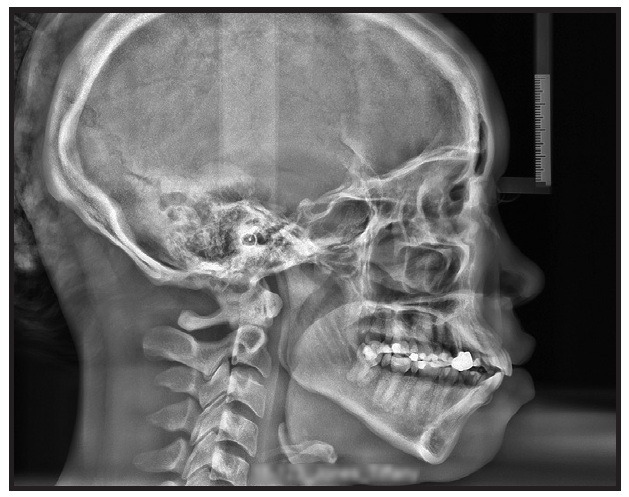

This patient presented with rotations from canine to canine in both arches (Fig. 5A). After 10 months of clear aligner therapy, the most severe rotation (the lower left lateral incisor) had been corrected, but a minor derotation of the lower right lateral incisor was still needed for ideal alignment (Fig. 5B). Even after an extra set of aligners, the rotation of the lower right lateral incisor was still unresolved (Fig. 5C).

Fig. 5 A. Patient with rotations from canine to canine in both arches before treatment. B. After 10 months of clear aligner therapy, minor rotation of lower right lateral incisor remaining. C. After extra set of aligners, rotation of lower right lateral incisor still unresolved.

Although premature contacts are easily ignored in an orthodontic practice, they can have serious effects on the tooth structure and support. Routine three-dimensional intraoral scans can easily show us where they are located. In this case, there was a strong contact between the upper right central incisor and lower right lateral incisor (Fig. 6). This contact should have been adjusted before more aligners were fabricated, but the premature contact with the distal marginal ridge of the upper right central incisor was clearly preventing derotation of the lower right lateral incisor (Fig. 7).

At this point, a selective occlusal adjustment was performed, and the rotations were entirely corrected with a few additional aligners.